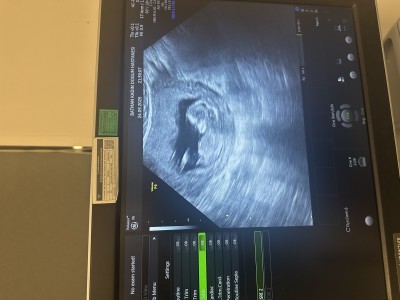

Arkadaşlar cinsiyet tahmininde bulunurmusunuz

Çok heyecanlıyım doktorum hala tam net bişey söylemedi her iki cinsiyetede benzetildi

Gebelik haftası 17.5

Erkeğe benziyor canım artık 17 haftalık olmuş net bir şey söylemesi gerekiyordu

Bence kız💕

Bacak arası goruntusu yok mu hiç, erkege benzettim

Pozisyonu uygun değil muhtemelen ama kesesi hem yuvarlak hem birazcık şekilli gibi bilemedim

Ben erkeğe benzettim  sağlıkla gelsin inşallah